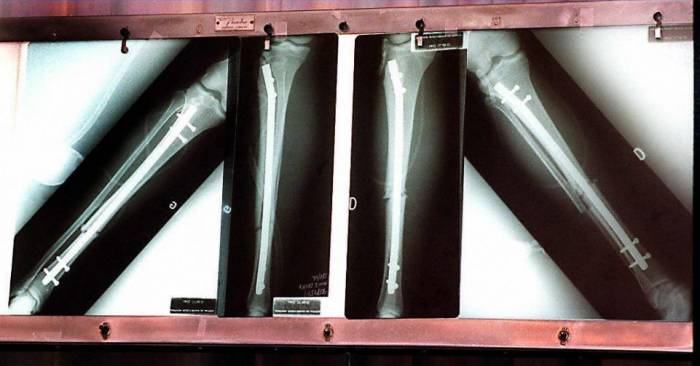

They can suffer burns and broken bones while feeling virtually no pain, meaning they often do not notice injuries.

Children with this condition often suffer oral cavity damage both in and around the oral cavity (such as having bitten off the tip of their tongue) or fractures to bones. Unnoticed infections and corneal damage due to foreign objects in the eye are also seen.

How they have never seen the condition as a negative, although it does have its downsides. For one thing, they often damage the roof of their mouths on hot drinks because they are unaware they are burning themselves. Similarly, her 24-year-old son has extremely delicate ankles due to numerous microfractures acquired while playing soccer.